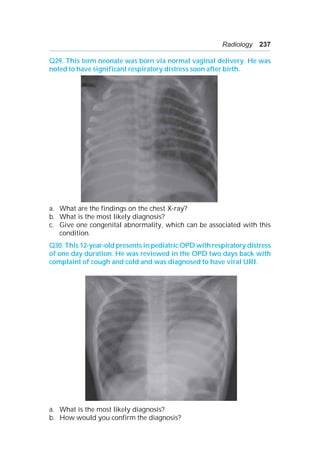

Cantrell’s pentalogy.

A 8:

a. Esophageal atresia.

b. Esophageal atresia with distal TEF (85%).

c. VATER/VACTREL.

A 9:

a. Absent clavicles.

b. Cleidocranial dysplasia.

c. i. Drooping shoulders.

ii. Open fontanelles, prominent forehead, mild short stature—because